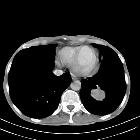

Round

atelectasis in sarcoidosis. CT image at the level of the right lower lobe bronchus shows an oval mass abutting the pleura, pulmonary vessels curving toward the opacity with parenchymal nodules.

atelectasis in sarcoidosis. Chest CT revealed a round pleural-based mass at the level of the right lower lobe with the characteristic comet tail sign of curving of vessels into the lesion with peribronchovascular and subpleural nodules.